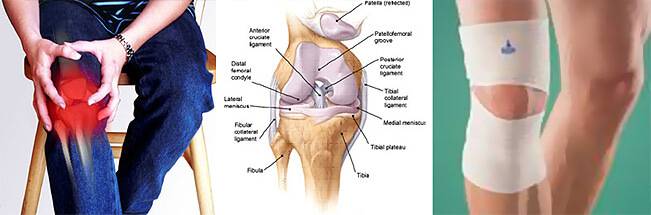

Анатомия коленного сустава: изучение анзерита и его влияния